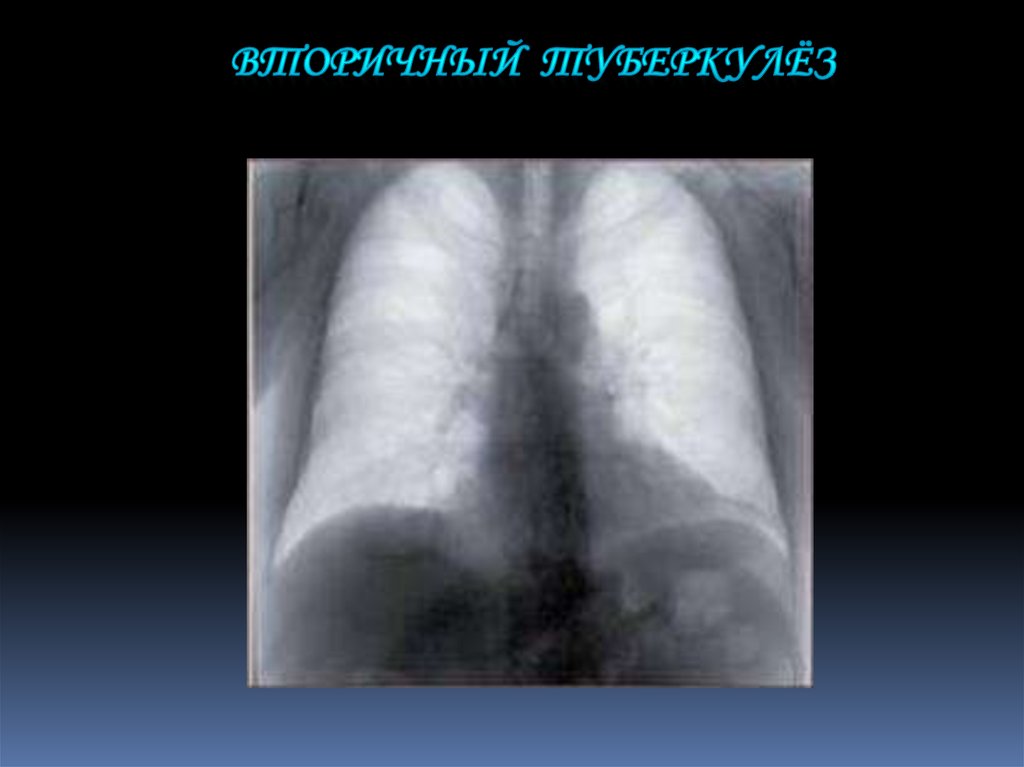

11. Вторичный туберкулёз

представляет собой

результат реактивации

эндогенной инфекции.

Болеют им

преимущественно

взрослые. Поражаются

обычно верхушечные и

задние сегменты

верхних долей лёгких.

Рентгенограмма органов грудной

клетки в прямой проекции больного

вторичным туберкулёзом.